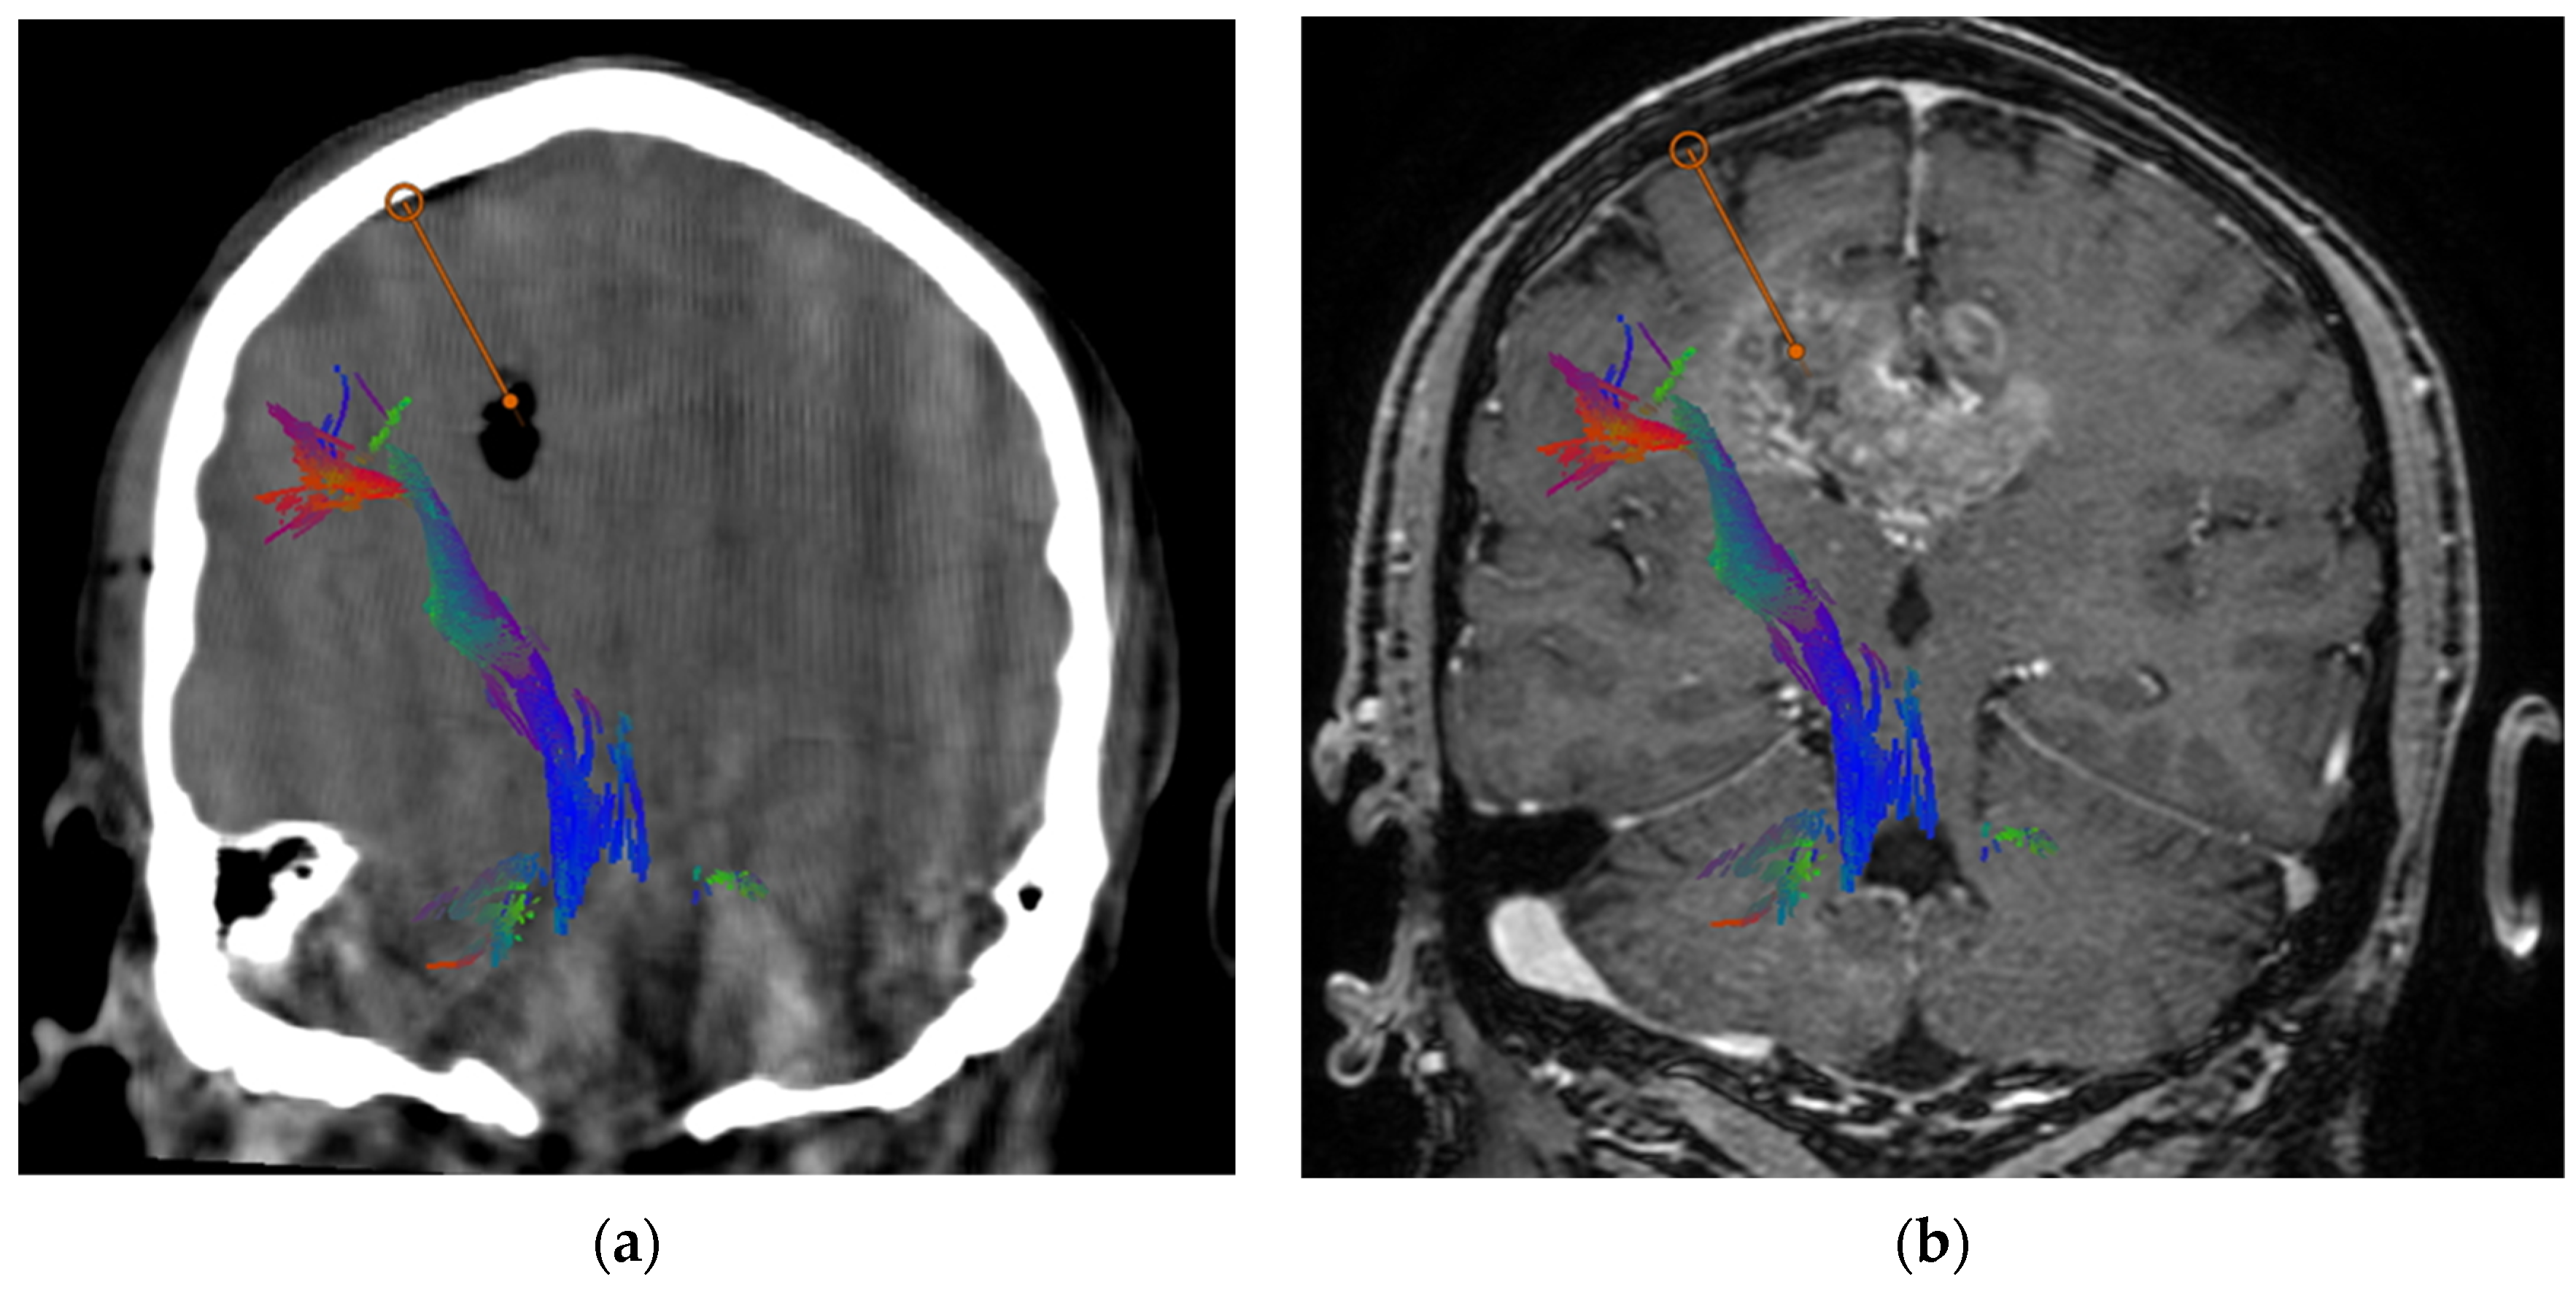

Figure 2.

Intraoperative CT scan (a) and pre-operative MRI (b) coronal images. Intraoperative CT shows the presence of air bubble at the planned target. Moreover, it rules out immediate bleeding. The red line represents the planned trajectory between the entry point and the target. Corticospinal tract is also displayed to confirm it has been avoided by the trajectory.

The safety of the procedure is also improved by integrating pre-operative tractography in the planning of trajectory, thus reducing the theoretical risk of damage to relevant fiber bundles like the corticospinal tract (Figure 2). A larger patient sample should be used to corroborate our impression that the recognition of the cortico-spinal tract (CST) may have a clinical impact in reducing the risk of motor impairment. A small hemorrhage may provoke a motor impairment, or it may be pauci-symptomatic; this may be a consequence of the distance of the needle trajectory from CST. The inclusion of tractography in the pre-surgical imaging protocol and the integration of the position of the CST among the various factors to be considered in the planning could be, in our opinion, a valuable help in some cases. The described case series is too small, and we have not encountered any hemorrhage, so we cannot test this hypothesis in the present study.